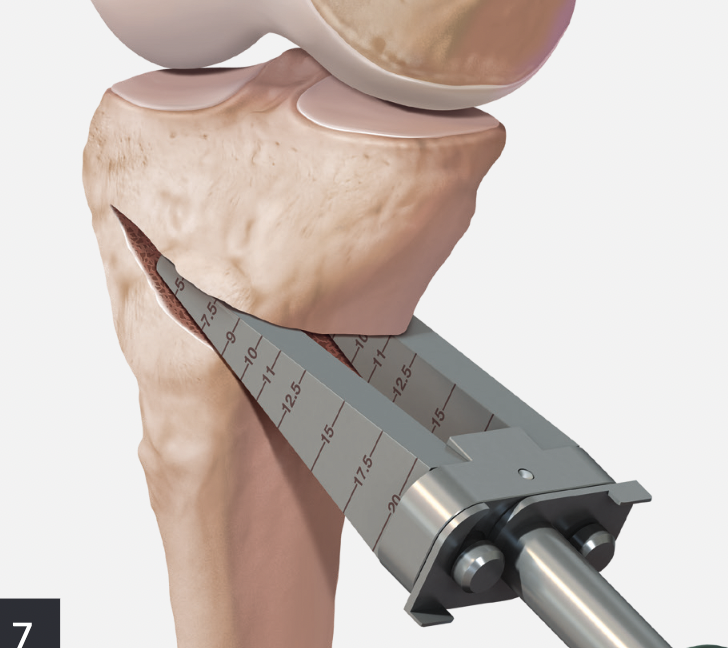

Oblique Osteotomy

- entry is 4 cm distal to joint line

- osteotomy must pass above tibial tuberosity

- aiming for proximal third of the fibula head

- to 10 mm of lateral cortex to avoid lateral hinge fracture

- stay 2 cm below the tibial plateau to avoid intra-articular fracture

- ensure osteotomy is parallel to joint line to avoid altering slope

- ensure complete posterior cortex

Opening of wedge

- stacked osteotomes / lamina spreader / wedged osteotomes

Arthrex wedged osteotomes